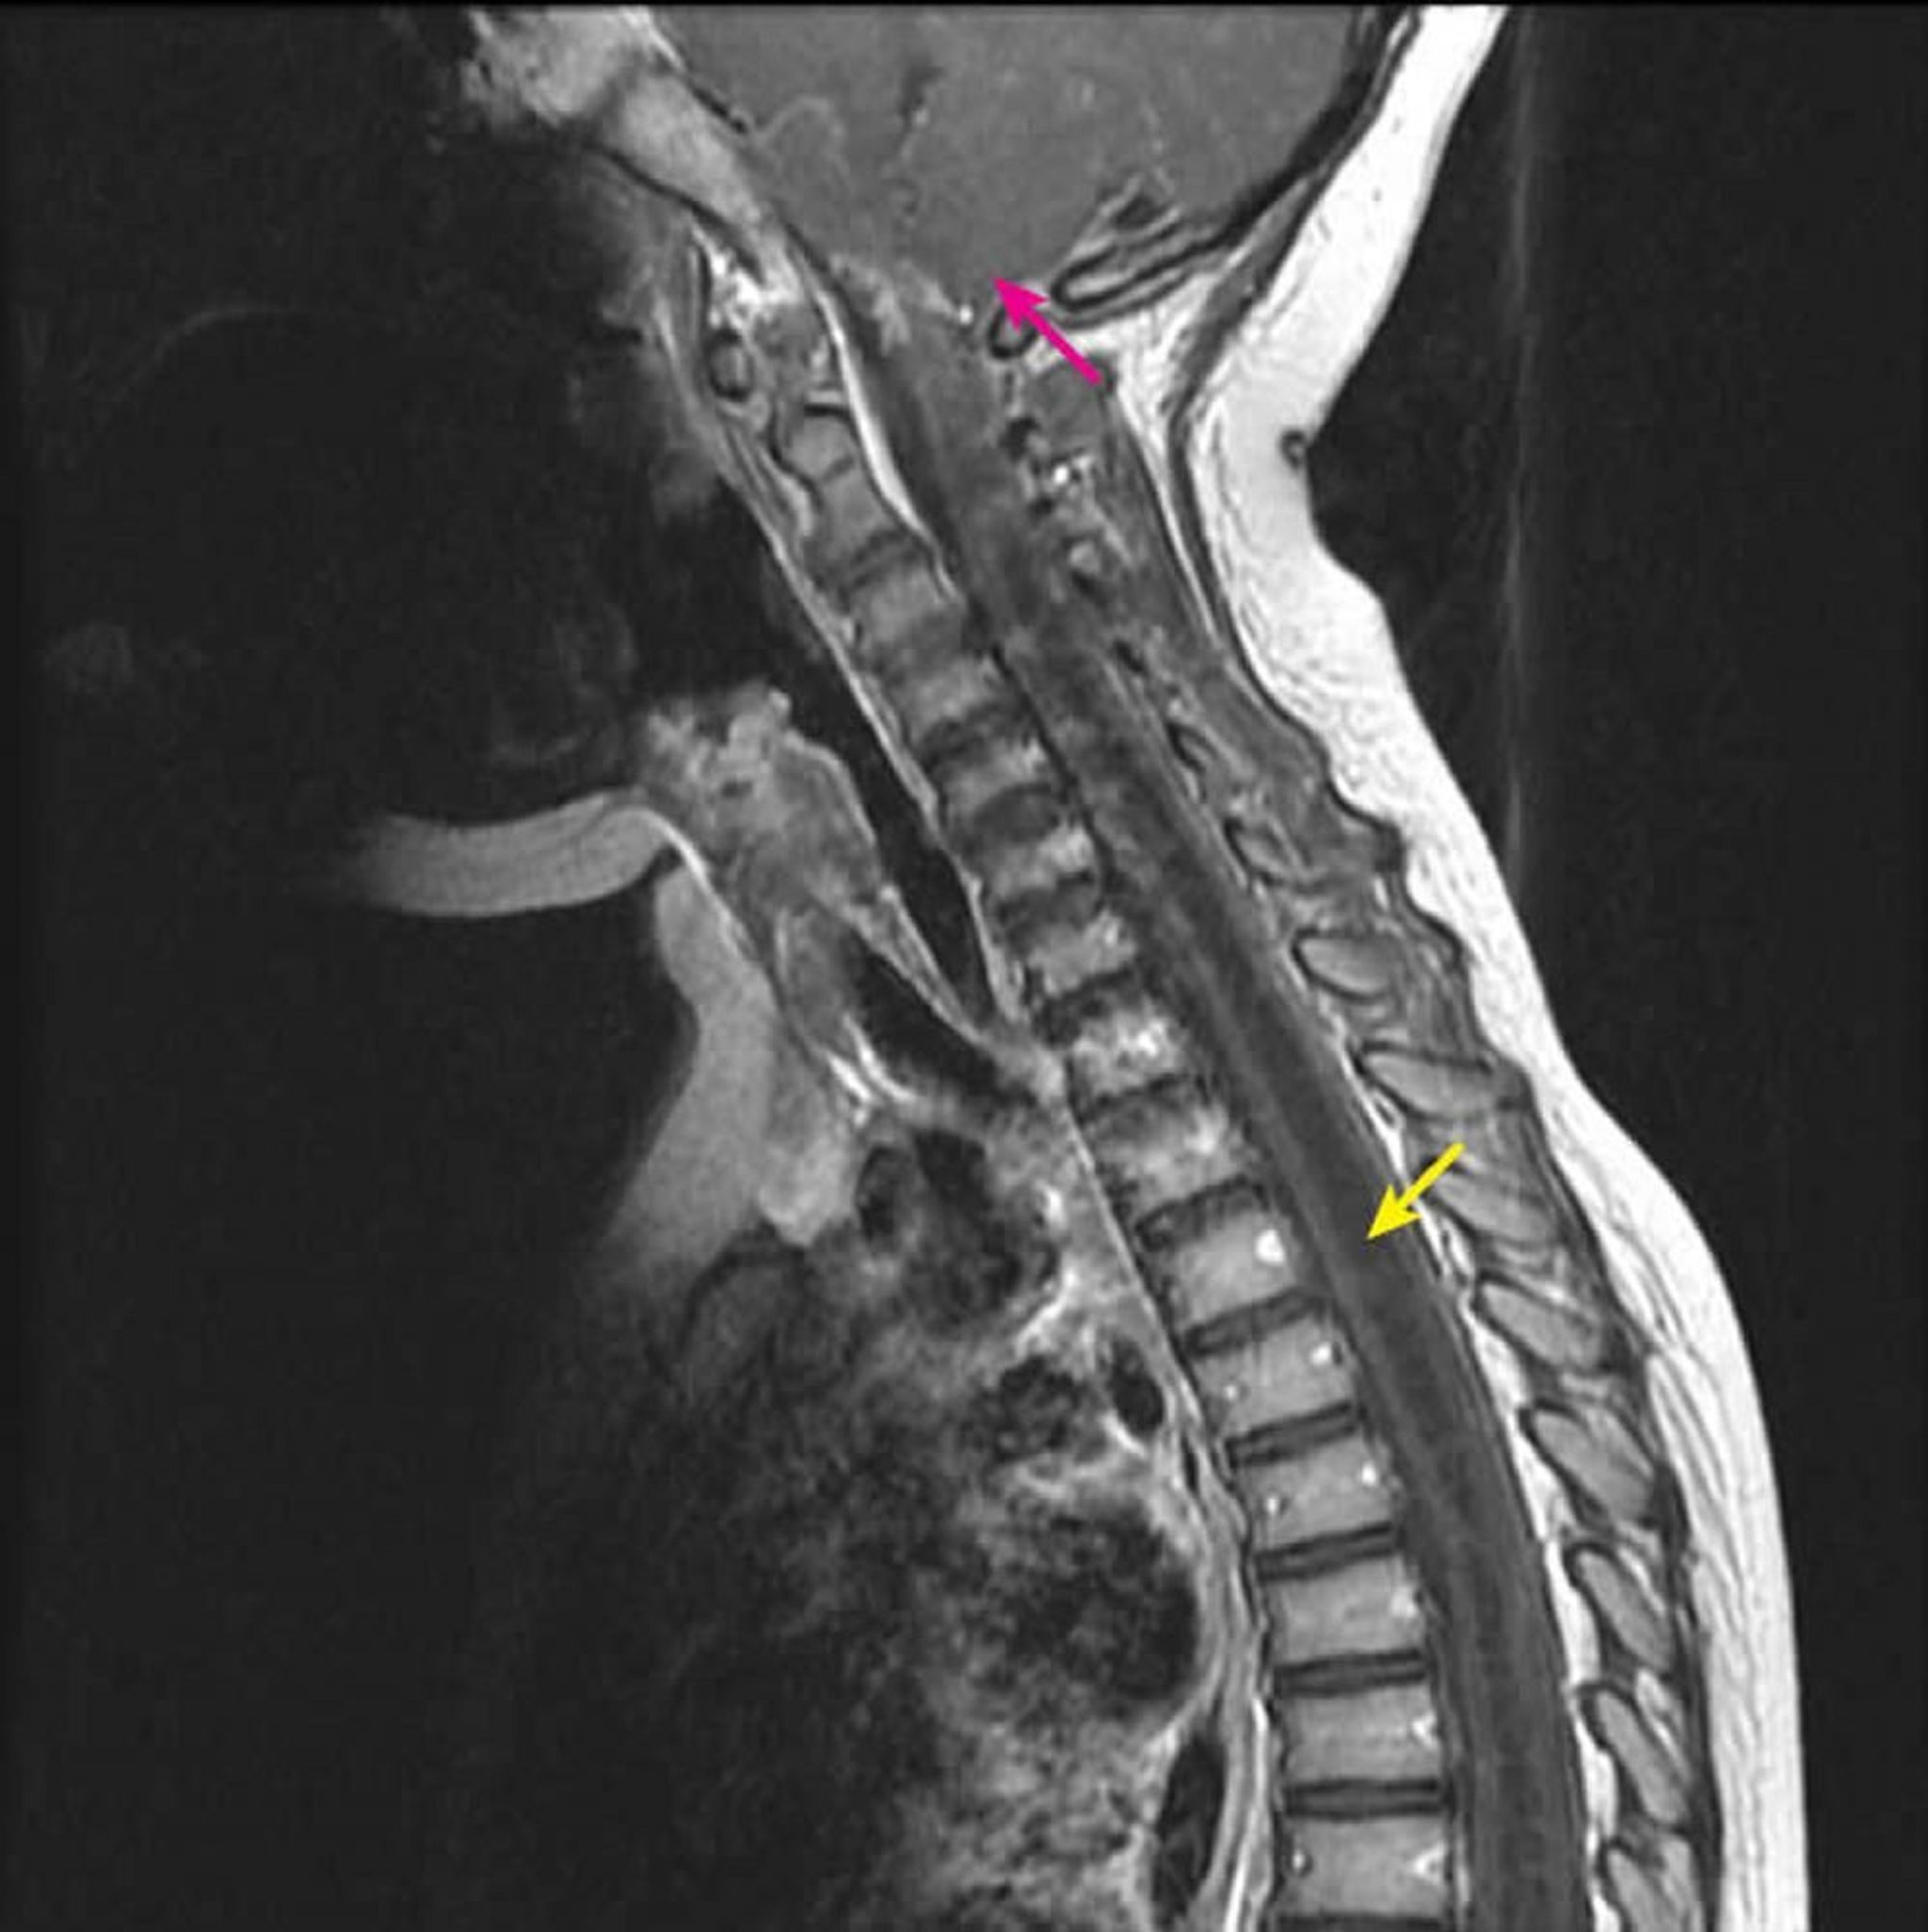

この造影後のMRI T1強調矢状断では,空洞症に特徴的な脊髄内部の大きな空洞が低信号域として認められる(黄色矢印)。キアリI型形成異常の患児では,空洞がC2-C3レベルから下方へと進展する(ピンク矢印)。脊髄空洞症(脊髄中心部以外の空洞)を画像検査でhydromyelia(脊髄中心部の空洞)と鑑別することはできないため,この所見はsyringohydromyeliaと定義される。

Courtesy of John Tsiouris, MD, Division of Neuroradiology, New York–Presbyterian Hospital/Weill Cornell Medical Center.